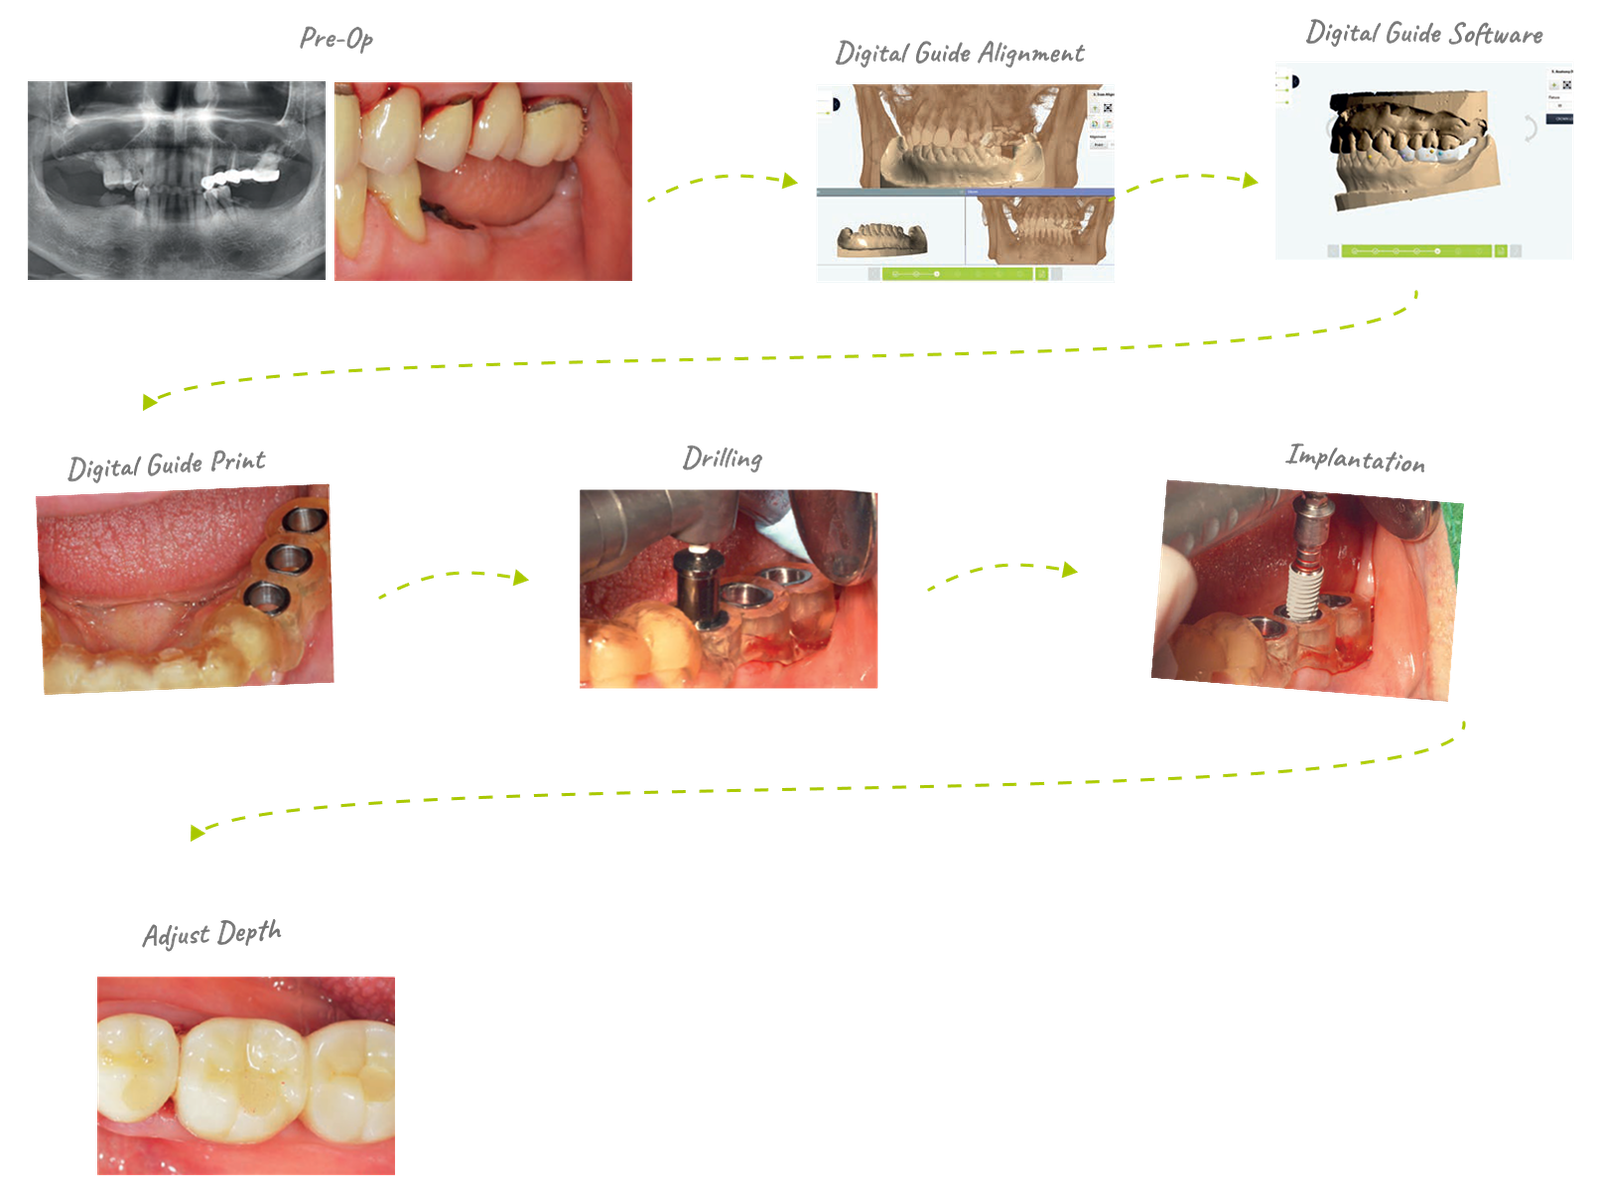

54yrs/Female | Implant Parts #35,36,37 | Fix Size: SuperLine FXS4012 | Guide Kit: Full Kit

It takes at least one week to produce through a request from the center, but if you design your own using Dentium Digital Guide Software, you can produce it within 30 minutes to an hour. When weeding the guide, pay attention to the ct alignment, and when making the guide, the undercut and border should be well set to fit the patient's mouth. It is recommended to use the anchor pin function for stability.